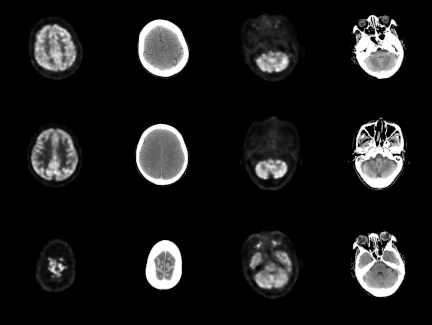

All data consist of paired PET/CT scan images, with each image having a depth of 16 bits. The processed PET and CT images were paired by filename and saved in \(256 \times 256\) pixel RGB image format, as in Fig. 2. After manual screening, we obtained 4,606 pairs of PET/CT images, with 4,230 pairs used for training and 376 used for testing.

Fig. 2. Visualization of the paired PET-CT image dataset. Columns 1 and 3 present PET images from the same subject, whereas Columns 2 and 4 display CT images corresponding to the same anatomical location. Consequently, each pair in this dataset comprises both PET and CT images.